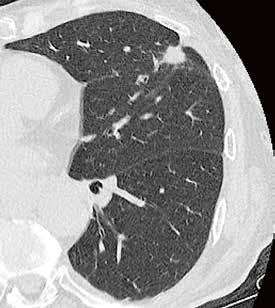

Fall 3:

Thorax-CT im Rahmen einer Lungenkrebsfrüherkennungsstudie. Die Voruntersuchung lag als externe kontrastmittelgestützte Thorax-CT vor. Bei der dosisoptimierten Low-Dose-CT liegt die Strahlenexposition nur noch im Bereich von zwei konventionellen Röntgenaufnahmen des Thorax, die Bildqualität ist für die Fragestellung nach Herdbefunden aber dennoch eindeutig ausreichend, selbst interstitielle Lungenveränderungen lassen sich hier noch beurteilen.

Prof. Dr. med. Johannes Weßling Zentrum für Radiologie, Neuroradiologie und Nuklearmedizin Abb. 3 a: kontrastmittelgestützte Thorax-CT, externe Untersuchung; DLP 216,0 mGy × cm / 3,9 mSv. Abb. 3 b: dosisoptimierte Low-Dose-Thorax-CT, Canon Aquilion Prime SP, Rekonstruktion: AiCE; DLP 13,9 mGy × cm / 0,25 mSv.